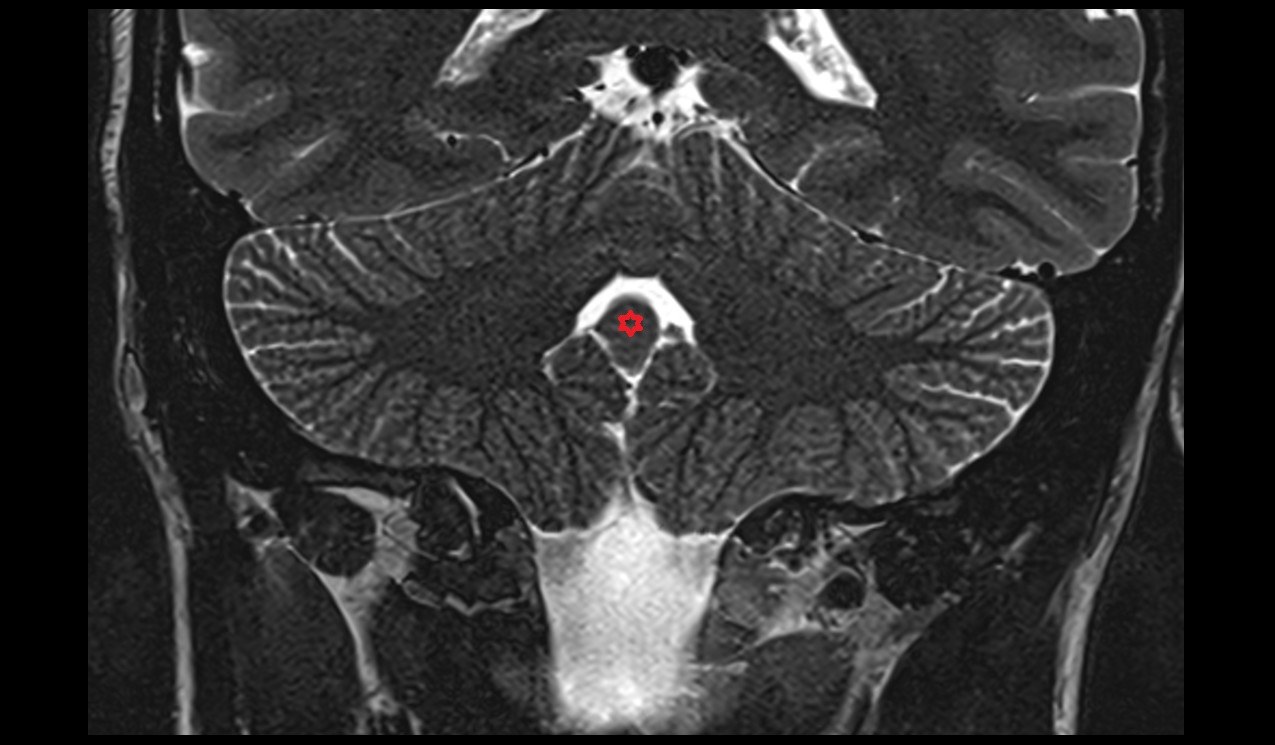

- Cerebellum

- Tonsil of cerebellum

- Cerebellar tonsil (H IX)